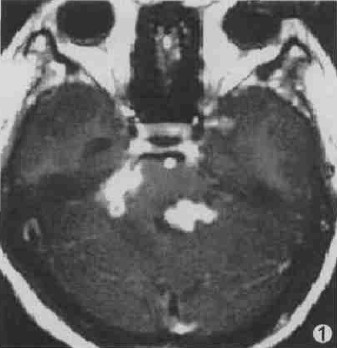

图1 第四脑室内结核瘤。

2.3 脑结核瘤的MRI影像学特征 ①成熟期19例。其中,干酪性实性中心结核瘤发现28个病灶,周围见轻度水肿带,T1WI呈低或等信号,T2WI呈等或高信号,增强呈环状或花环状强化,强化环壁厚度0.5~1.5cm;干酪性液性中心结核瘤发现50个病灶,周围无或有轻度水肿带,T1WI瘤壁呈等或略低信号,瘤体内呈混杂信号,T2WI瘤壁呈等或略高信号,瘤体内呈混杂信号,增强呈环状强化,壁欠光滑且厚薄不均匀,厚度约0.5~1.0cm。+